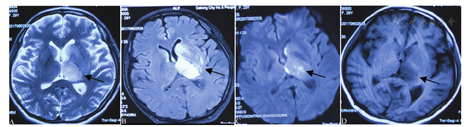

患者女性,28岁,主因"头痛5 d,言语不利、右侧肢体无力2 d,意识不清1 d"于2017年6月3日急诊以"颅内病变"收入首都医科大学宣武医院。现病史:患者5月30日(顺产后第6天,孕期及产程平顺)无明显诱因出现全头持续性胀痛,无恶心呕吐,无肢体乏力,经治疗头痛不能缓解。6月2日凌晨患者出现言语含糊不清、右侧肢体无力,在当地医院就诊,头颅MRI示左侧基底节T2、液体衰减反转恢复序列(fluid-attenuated inversion recovery, FLAIR)、弥散加权成像(diffusion-weighted imaging, DWI)高信号以及T1低信号影,病灶部分强化(图1)。6月3日早晨患者出现意识不清及全面惊厥性癫痫持续状态,表现为四肢僵硬伴牙关紧闭,抽搐持续1 h缓解,但意识仍未恢复,转至首都医科大学宣武医院。既往体健,孕2产2,均为顺产,无吸烟饮酒史。否认传染病、遗传病及类似疾病史。发病前无感染发热史,发病以来饮食较少,留置导尿,体重未见明显减轻。

A~D分别提示左侧基底节T2、液体衰减反转恢复序列(FLAIR)、弥散加权成像(DWI)高信号以及T1低信号影,符合静脉性梗死改变,且位于直窦投影区(黑色箭头)